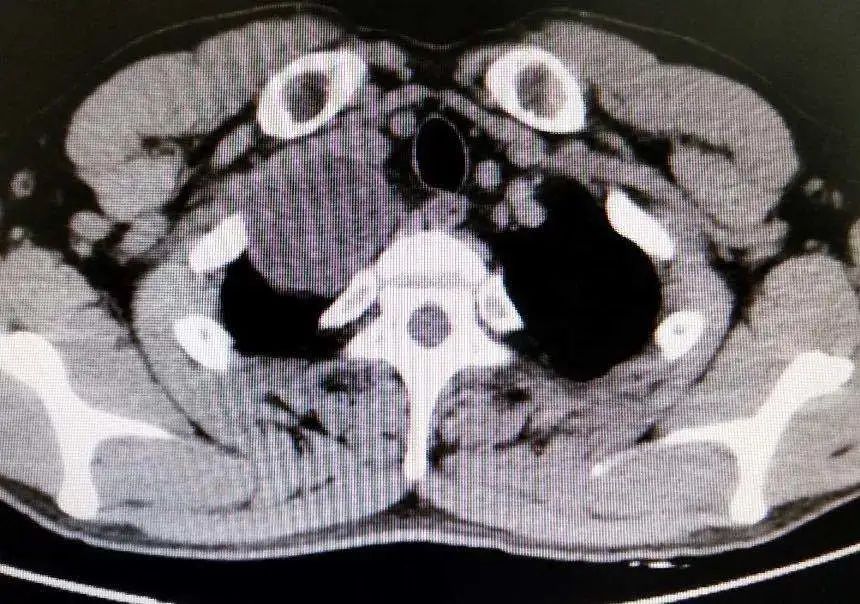

郑志民医生为苏先生进一步做了检查并询问了他的病史后,初步诊断为“右上纵隔巨大肿瘤,神经鞘瘤可能性大”,需要住院手术治疗。在苏先生住院进行了一系列检查后, 郑志民医生发现,他体内的肿瘤不仅体积大(直径约7cm),而且位置深(胸膜顶),紧邻大血管及右侧锁骨,手术难度大,遂决定向杭州的树兰医院胸外科朱理主任汇报并立即组织胸外科全科进行科内讨论。

手术当日,一场经过充分准备的“战斗”在手术室拉开序幕。在麻醉科的安全守护下,树兰医院朱理主任、晋医郑志民主任团队紧密配合,在两位主任强强联手下,在没有损伤到血管,没有劈开右侧锁骨、没有中转开胸的情况下,快速而巧妙地解决“战斗”。仅用时1个多小时,出血仅几毫升,切口3-4cm的微创手术下,患者右上纵隔肿瘤被完整切除,完成一场精彩的“探囊取物”。术后病理诊断证实与术前一致,为神经鞘瘤。

据郑志民主任医师介绍,苏先生的肿瘤巨大,且位置深,位于胸膜顶,紧邻大血管及右侧锁骨,这个位置的肿瘤对胸外科医生是一个巨大的挑战,锁骨切开是一个选择,但是考虑到手术如果采取切断锁骨的方式,会对锁骨的损伤非常大,手术风险性非常大,稍有不慎,就会损伤血管造成大出血的状况。这就要求主刀医生具有丰富的手术经验和过硬的显微外科技术。所幸在树兰医院朱理主任的助力下,经过1个半小时的努力,在微创下手术顺利完成,完成一个精彩的“探囊取物”。